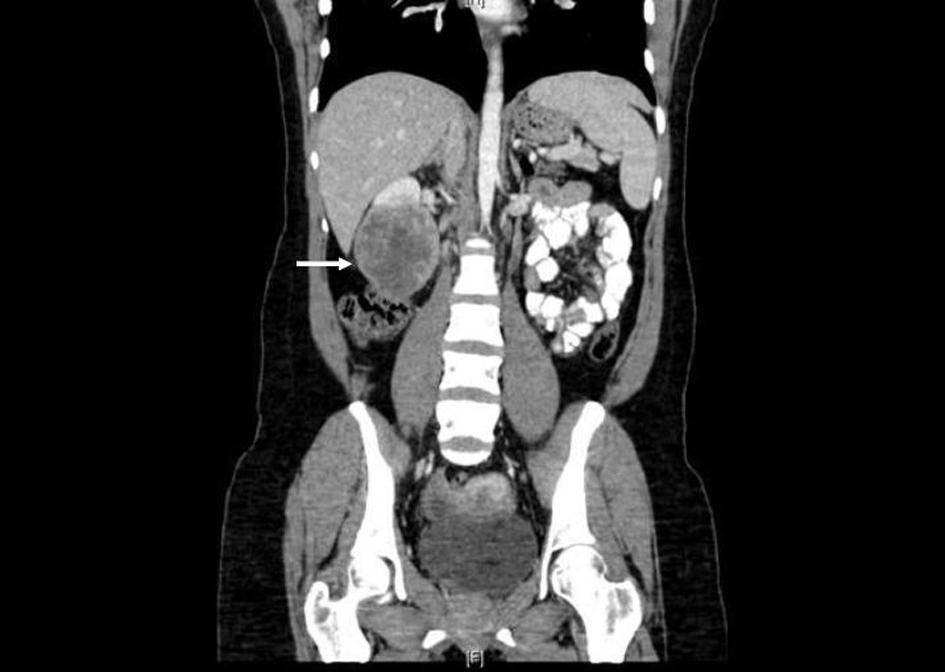

Prior to treatment, she underwent contrast enhanced staging CT of the abdomen and pelvis which revealed a 6.7 × 6.9 cm mass arising from the lower pole of the right kidney (Fig. 3, 4). Given the patient’s young age, history of sickle cell trait, radiologic findings of a large renal mass, multiple lung and breast nodules as well as the histological picture, the diagnosis of metastatic renal medullary carcinoma was considered. At this time, the original breast core biopsies were re-reviewed. Histological findings of prominent neutrophilic infiltrate closely associated with the tumor and sickled erythrocytes were identified. An additional immunohistochemical panel of PAX 8, vimentin, gross cystic disease fluid protein (GCDFP), Oct 3/4 and INI1 (BAF47) was performed. Positive expression of PAX 8 (nuclear) (Fig. 1b), vimentin (cytoplasmic and membranous), Oct3/4 (nuclear) (Fig. 1c) and loss of INI1 expression (Fig. 1d) in tumor cells confirmed the diagnosis of renal medullary carcinoma metastatic to breast [6-8].

![]() Click for large image | Figure 4. Coronal CT (with oral and intravenous contrast enhancement) showing large heterogeneously enhancing mass replacing lower pole of the right kidney. |